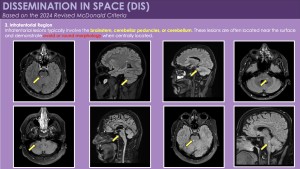

1. Dissemination in Space (DIS): Updated MRI Definition

According to the 2024 McDonald criteria, dissemination in space is demonstrated by typical demyelinating lesions in at least two of five anatomical regions:

- Infratentorial